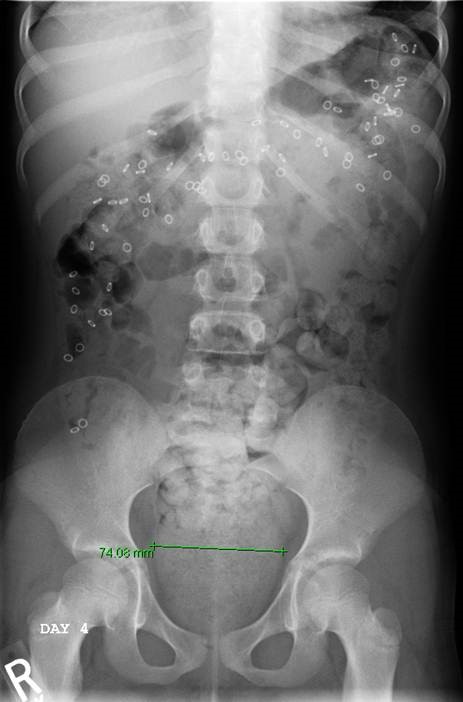

If your child has functional constipation and is not responding well to a bowel management program, pediatric colorectal specialists and gastroenterologists will perform a series of diagnostic tests to determine the underlying cause of the condition.

If your child is a candidate for surgery, the type of surgery your child will need and when to perform it is based on a comprehensive evaluation of the anorectal and colorectal anatomy and physiology.